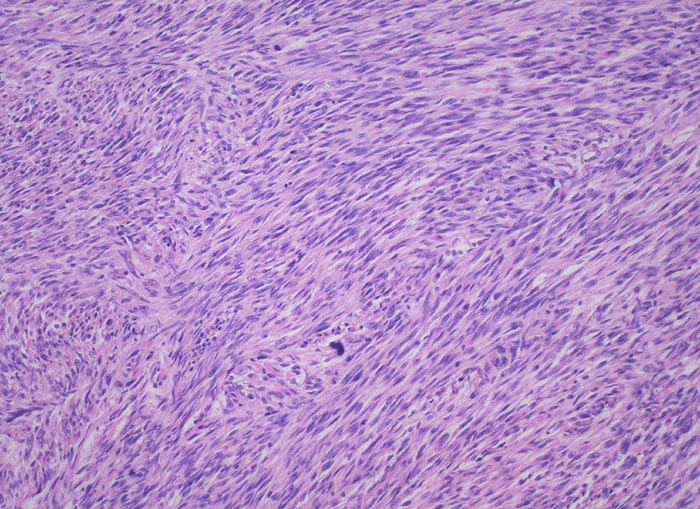

• Die spindeligen Tumorzellen mit längsovalen Kernen und reichlich kräftig eosinophilem Zytoplasma bilden Faszikel ähnlich wie nicht neoplastische glatte Muskulatur.

• Alle drei histologischen Malignitätskriterien sind erfüllt:

• Bereits in der Übersicht (10x) erkennbare diffuse signifikante Zellatypien.

• Vermehrt Mitosen: mehr als 10 Mitosen / 10 HPF (40x). Das sollte der Kliniker dem Pathologen mitteilen: